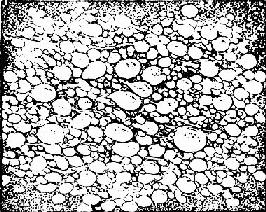

来源于胚胎的滋养细胞。由于绒毛水肿增大,形成大小不等的水泡,相连成串,状似葡萄,故称葡萄胎(图167)。

图167 水泡状胎块